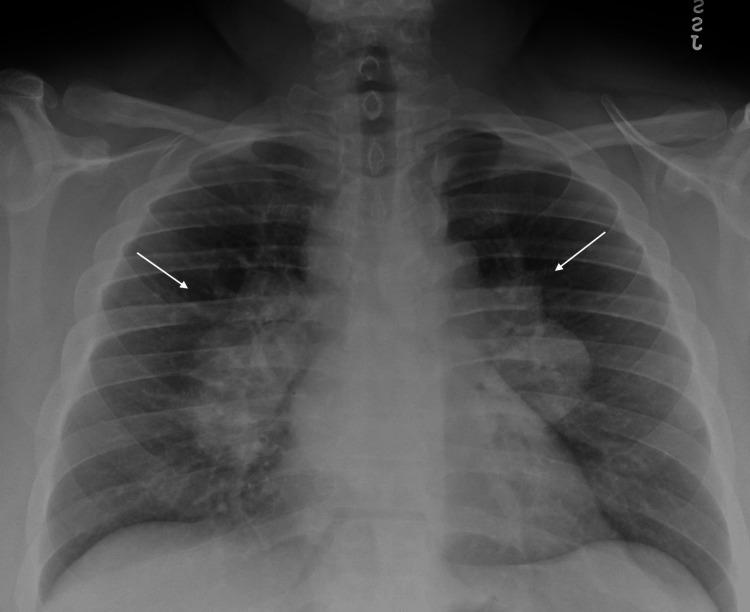

Sarcoidosis is a multisystem inflammatory disorder characterized by the formation of non-caseating granulomas. Hematological manifestations such as thrombocytopenia are unusual presentations of the disease. Various theories have been proposed for the development of thrombocytopenia in patients with sarcoidosis such as decreased production in bone marrow caused by granuloma formation, hypersplenism, and immune thrombocytopenia (ITP). We present a case of a 30-year-old African American male with ITP secondary to sarcoidosis who presented with a sudden onset of buccal mucosa and mucocutaneous bleeding and was found to have severe thrombocytopenia with values reaching as low as 1000/uL without prior history of easy bruising or bleeding. Overall, our patient had dyspnea, mucocutaneous bleeding, and was found to have mediastinal and hilar adenopathy, isolated thrombocytopenia, no splenomegaly, and non-necrotizing granulomas in the lymph nodes. The patient received platelet transfusions without initial response and received intravenous immunoglobulin (IVIG), romiplostim, and steroids with subsequent improvement in the platelet count after sufficient administration of a treatment regimen of approximately one week. Confounding factors that resulted in diagnostic uncertainty of our patient presentation included travel history with prophylactic antimalarial medications, doxycycline usage, only slightly elevated Angiotensin-Converting Enzyme (ACE) levels, and imaging features concerning metastatic disease vs. lymphoma. The clinical diversity of sarcoidosis often leads to diagnostic uncertainty and treatment delays due to its resemblance to other more common disorders. This is a novel case report of the earliest temporal presentation of severe thrombocytopenia and sarcoidosis in an African American male reported in the literature.

结节病是一种多系统炎症性疾病,其特征是形成非干酪样肉芽肿。血小板减少等血液学表现是该疾病不常见的表现形式。关于结节病患者血小板减少的发生提出了各种理论,例如肉芽肿形成导致骨髓生成减少、脾功能亢进和免疫性血小板减少症(ITP)。我们报告一例30岁非裔美国男性病例,该患者因结节病继发ITP,表现为颊黏膜和皮肤黏膜突然出血,发现有严重血小板减少,数值低至1000/μL,既往无易瘀伤或出血史。总体而言,我们的患者有呼吸困难、皮肤黏膜出血,发现有纵隔和肺门淋巴结肿大、孤立性血小板减少、无脾肿大以及淋巴结中有非坏死性肉芽肿。患者接受血小板输注后最初无反应,随后接受静脉注射免疫球蛋白(IVIG)、罗米司亭和类固醇治疗,在给予约一周的治疗方案后血小板计数随后有所改善。导致我们患者临床表现诊断不确定性的混杂因素包括有预防性抗疟药物的旅行史、使用强力霉素、血管紧张素转换酶(ACE)水平仅略有升高以及关于转移性疾病与淋巴瘤的影像学特征。结节病的临床多样性常常因其与其他更常见疾病相似而导致诊断不确定性和治疗延迟。这是文献中报道的首例非裔美国男性最早出现严重血小板减少和结节病的病例报告。